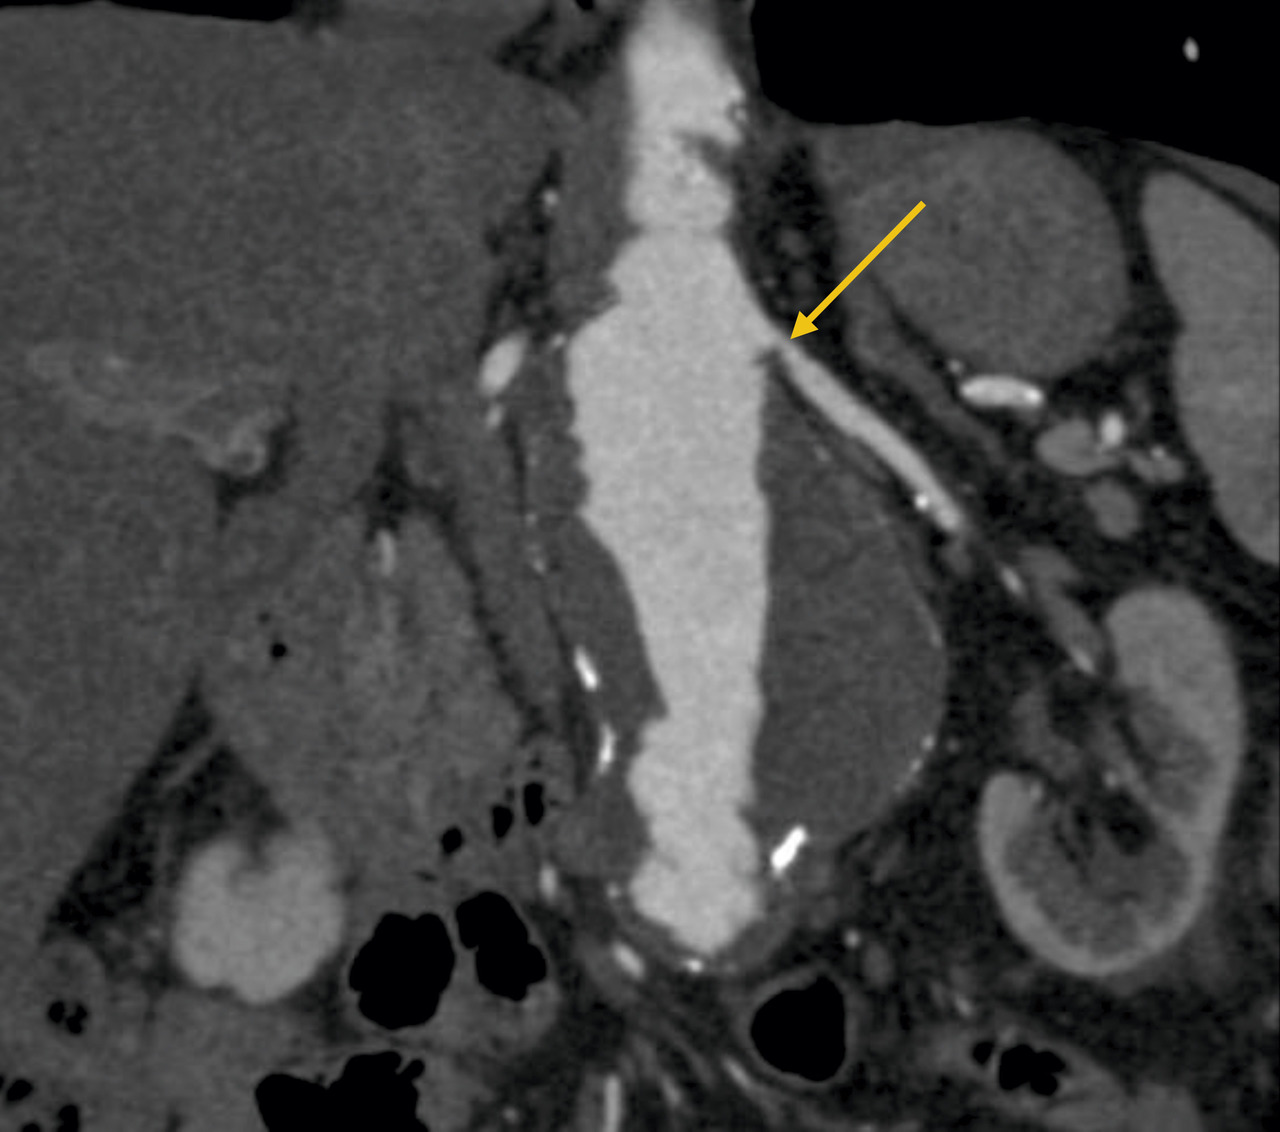

L’échographie-Doppler, l’angio-tomodensitométrie (angio-TDM [fig. 2] et l’angio-imagerie par résonance magnétique (angio-IRM) [fig. 3] permettent le diagnostic de sténose de l'artère rénale. Ils estiment à la fois le degré de sténose (exprimé en pourcentage de réduction du diamètre) et l’impact sur la vascularisation d’aval. Ces 3 examens sont validés et recommandés en première intention. Leur utilisation dépend de l’accessibilité et des habitudes locales. Il est à noter que l’écho-Doppler, très sensible et spécifique dans la sténose de l'artère rénale athéromateuse sous réserve d’un opérateur entraîné, est de sensibilité imparfaite dans la fibrodysplasie, dans laquelle l’angio-TDM est l’examen de référence.

Dans la sténose de l'artère rénale athéromateuse, on retrouve une plaque habituellement unique, plus une moins calcifiée, ostiale, proximale ou tronculaire, responsable d’une réduction du diamètre endoluminal d’une ou des artères rénales (fig. 2 et 3).